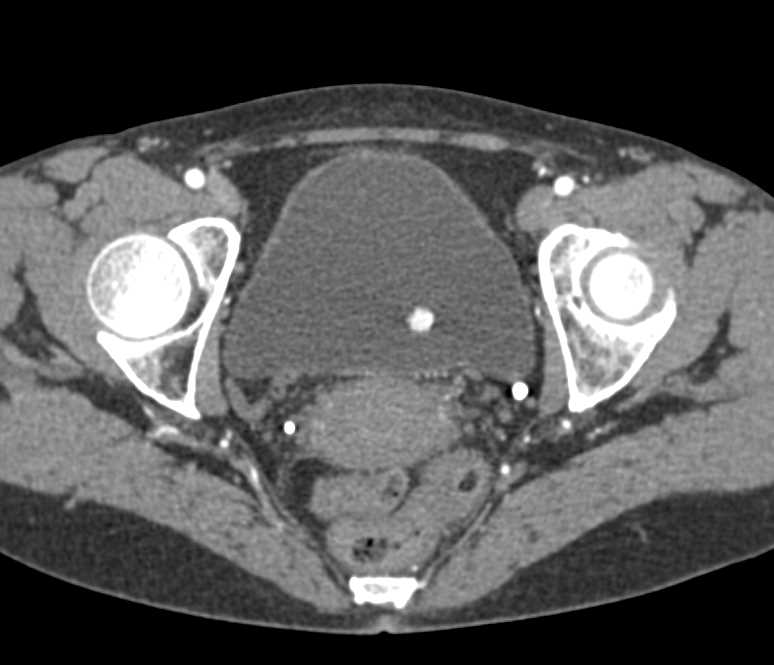

Bladder Cancer with Active Bleed